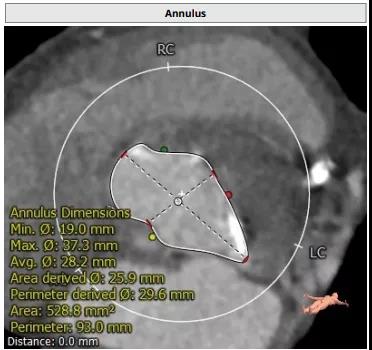

病例3(经颈动脉TAVI)

患者男性,67岁,头晕伴胸闷、胸痛6月余,术前心脏超声提示主动脉瓣增厚钙化伴重度狭窄,峰值流速4.9m/s,峰值压差94mmHg,平均跨瓣压差59mmHg,瓣口面积0.6cm2。CT显示主动脉瓣为Type I型二叶瓣,瓣叶边缘及左右冠瓣融合嵴严重钙化,致瓣口极度细窄。瓣环面积528.8mm2,测算直径25.9mm,左冠脉开口高度14.4mm,右冠脉开口高度17.5mm。患者合并重度肺气肿、多发肺大泡、支气管扩张,肺功能极差,静息状态下氧饱和度仅约80%,STS评分8.6%,属于外科手术高风险患者。

主动脉瓣瓣环 Type I型二叶瓣

瓣叶及左右冠瓣融合嵴重度钙化 重度肺气肿、多发肺大泡